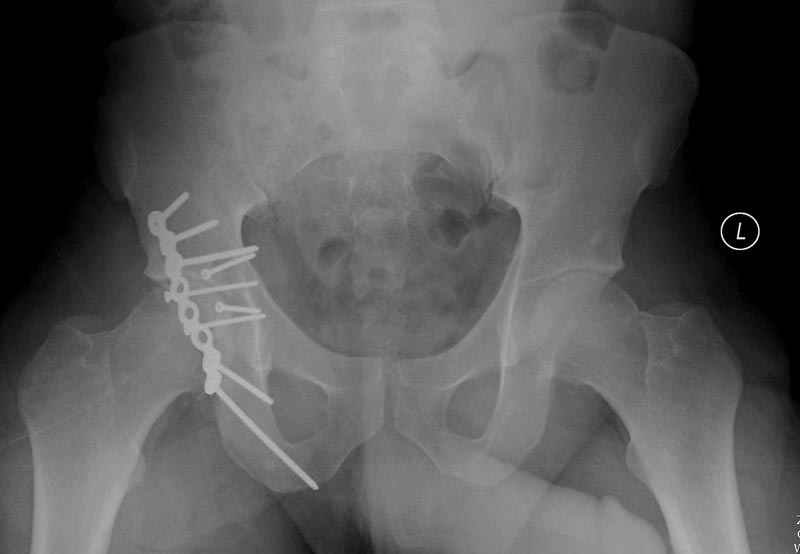

Выставлена на обсуждение (только одна проекция) рентгенограмма больного 25 лет, поступившего в приемное отделение, молодой дежурный врач сомневается в тактике лечения и спрашивает совета.

5:24 Рентгенограмма таза, вызывают врача ортопеда (снимок N1), его диагноз: закрытый переломо-вывих правого тазабедренного сустава, получает добро на закрытую репозицию в приемном отделении

N 2

6:20 ответстенный врач принимает решение о репозиции в условиях операционной, предупреждаются родственники и больной, что при неудачной закрытой репозиции, о возможности открытой репозиции и фиксации задней стенки вертлужной впадины.

7:30 начало операции, больной на спине, попытка репозиции после анестезии N3, укладка больного на боку, доступ Kocher- Langenbeck, состояние седалищнего нерва около 2.5см кровоподтек, через joistick головка бедра приподнята, освобовождение сустава, фрагмент заднего края более 3х4 см репонирован на свое место. После промывания

сустава, репозиция вывиха (N4), фиксация фрагмента 2.7(4) мм шурупами и допольнительно реконструктивной пластиной на 8 дырок, фиксация 3.5мм шурупами проксимально и дистально.

Интраоперционные N5 косая запирательная и N6 подвздошный снимок

11:50 больной в послеоперационной, рентгенограмма N7, компьютерная томограмма в тот же день N8-10